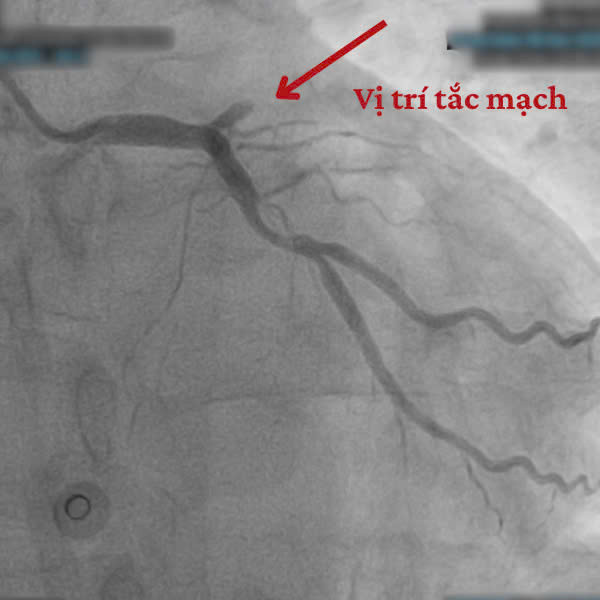

Ngay sau khi ổn định các chỉ số sinh tồn, người bệnh được đưa vào phòng Can thiệp Tim mạch. Qua hình ảnh chụp mạch vành, các bác sĩ phát hiện tắc hoàn toàn ngay sau lỗ động mạch liên thất trước (mạch máu chính nuôi tim).

![]() |

| Hình ảnh trên thiết bị can thiệp |